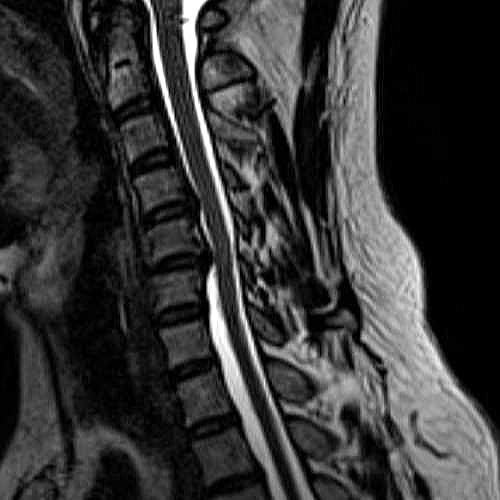

頚部MRI拡大画像

@ 横から撮影

↓脊椎  ↓脊髄

5番目の椎間板が新たに後方突出し、神経根を圧迫・刺激している。

6番目の椎間板が突出、潰れた状態で硬化。

脊柱管が狭窄し、突出、潰れた椎間板と骨棘(トゲ状態になった骨)が、

脊髄の左側を圧迫・刺激している。